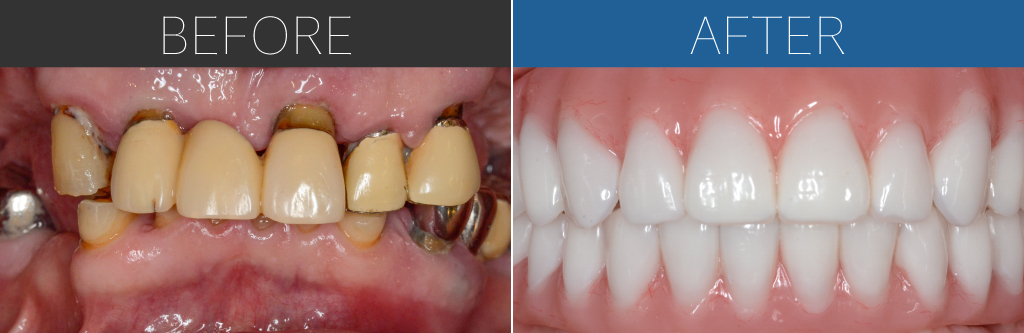

– Upper:All-on-4 + Zygoma + Pterygoid implants

– Lower:All-on-4

Age:60s

| 治療内容 | 上顎は左側にザイゴマインプラントを加え、両側にテリゴイドインプラントを併用。下顎は基本的な4本埋入によるオールオン4。上下ともに即時荷重により手術当日に仮歯を固定。 |